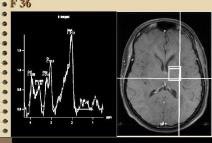

5、H磁共振波谱(H-MRS)检查,H-MRS检查对脑肿瘤、前列腺癌、乳腺癌等肿瘤的诊断与鉴别诊断有很大帮助,也用于研究其他部位肿瘤与非肿瘤性病变的鉴别。